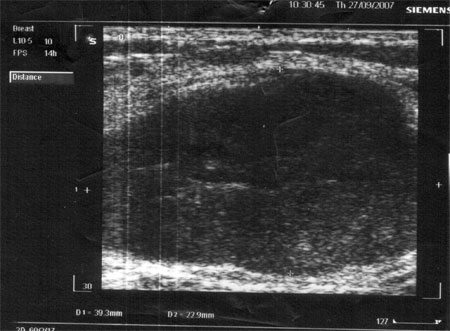

УЗИ при фиброаденоме молочной железы